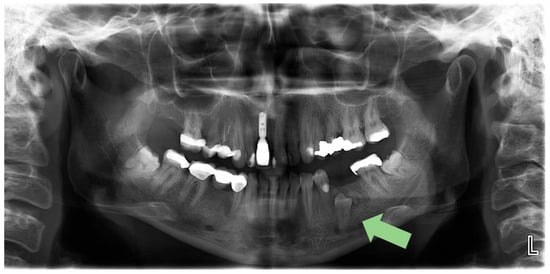

2.1. Initial Visit, Radiographic Evaluation and Diagnosis